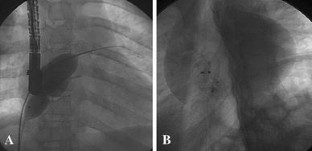

Fig. 2